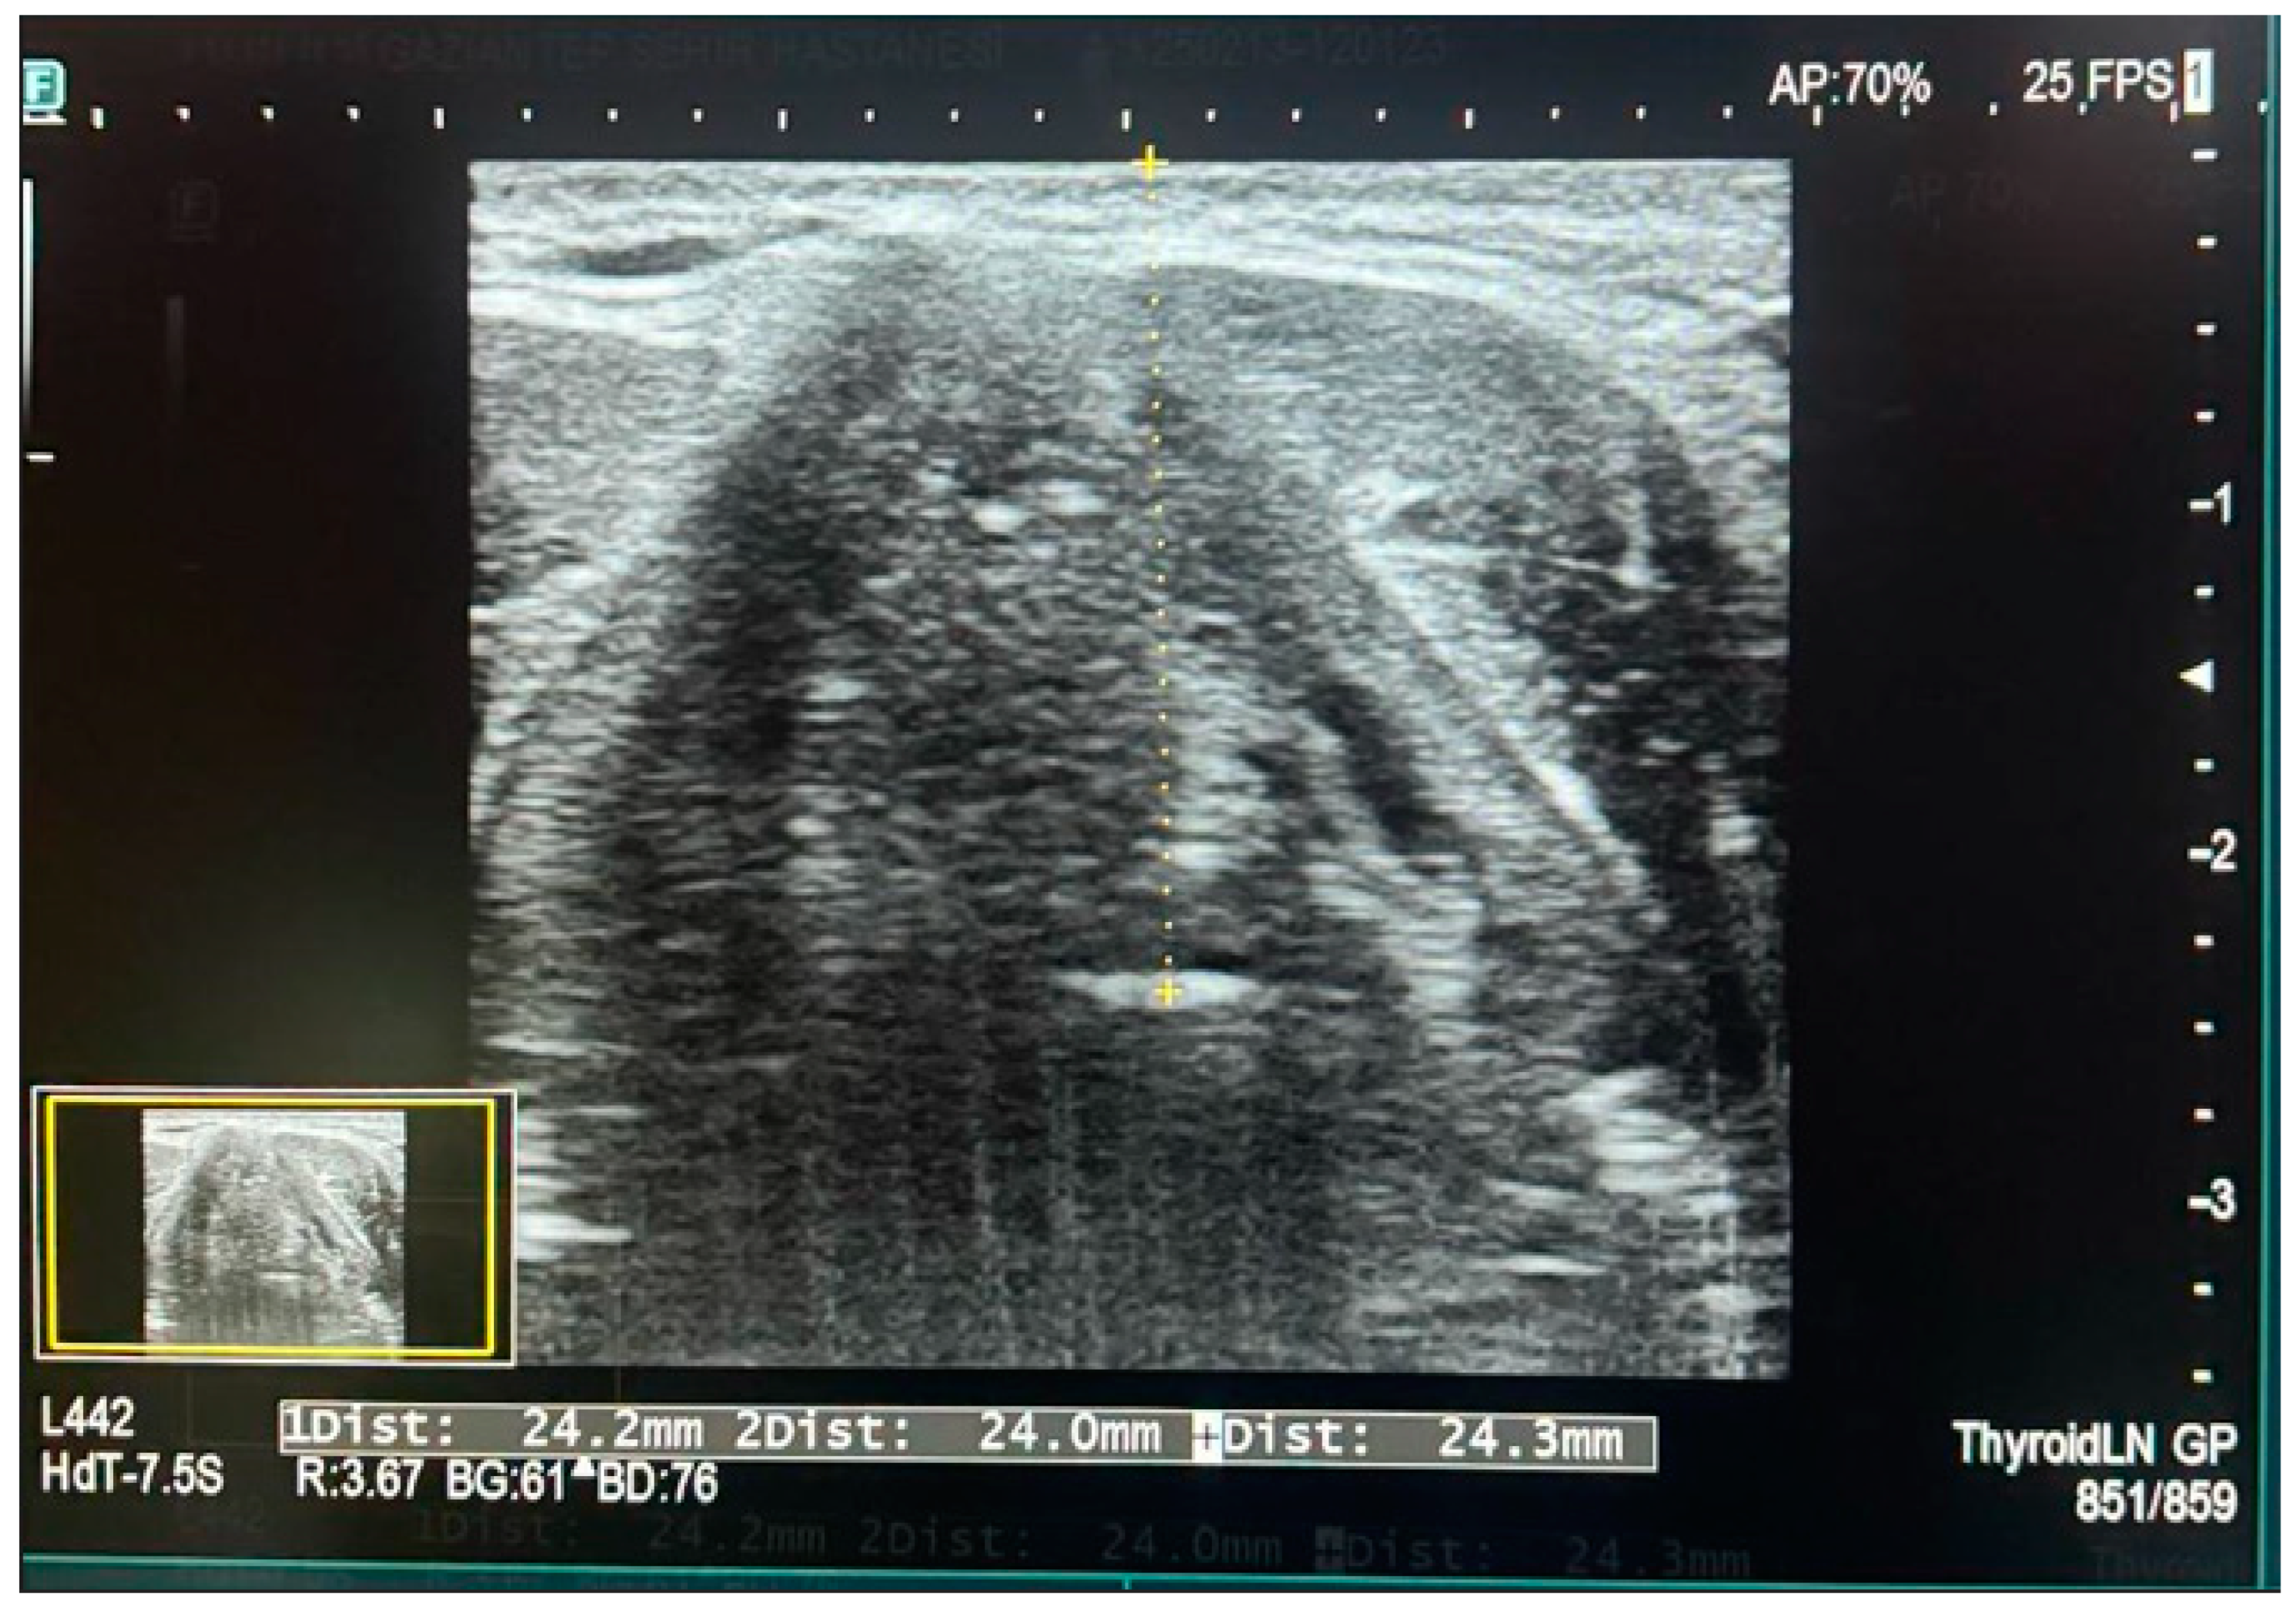

Ultrasound measurements were performed by the same sonographer each time, using different degrees of cephalad and caudal angulation in the transverse plane. A Sonosite M-Turbo ultrasound device equipped with a 10–13 MHz linear transducer was used for the measurements. The ultrasound probe was positioned at the thyrohyoid membrane level on the neck. The epiglottis was identified as a curved, hypoechoic structure in the transverse plane at the thyrohyoid membrane level. Once all soft tissue structures were anatomically identified, the distance from the skin to the epiglottis (DSE) was measured. For each individual, three separate measurements were taken: one at the midline, one on the right side, and one on the left side of the epiglottis. The average of these three measurements was recorded as the final value (see Figure 2).

Figure 2. Measurement of skin-to-epiglottis distance via ultrasound.